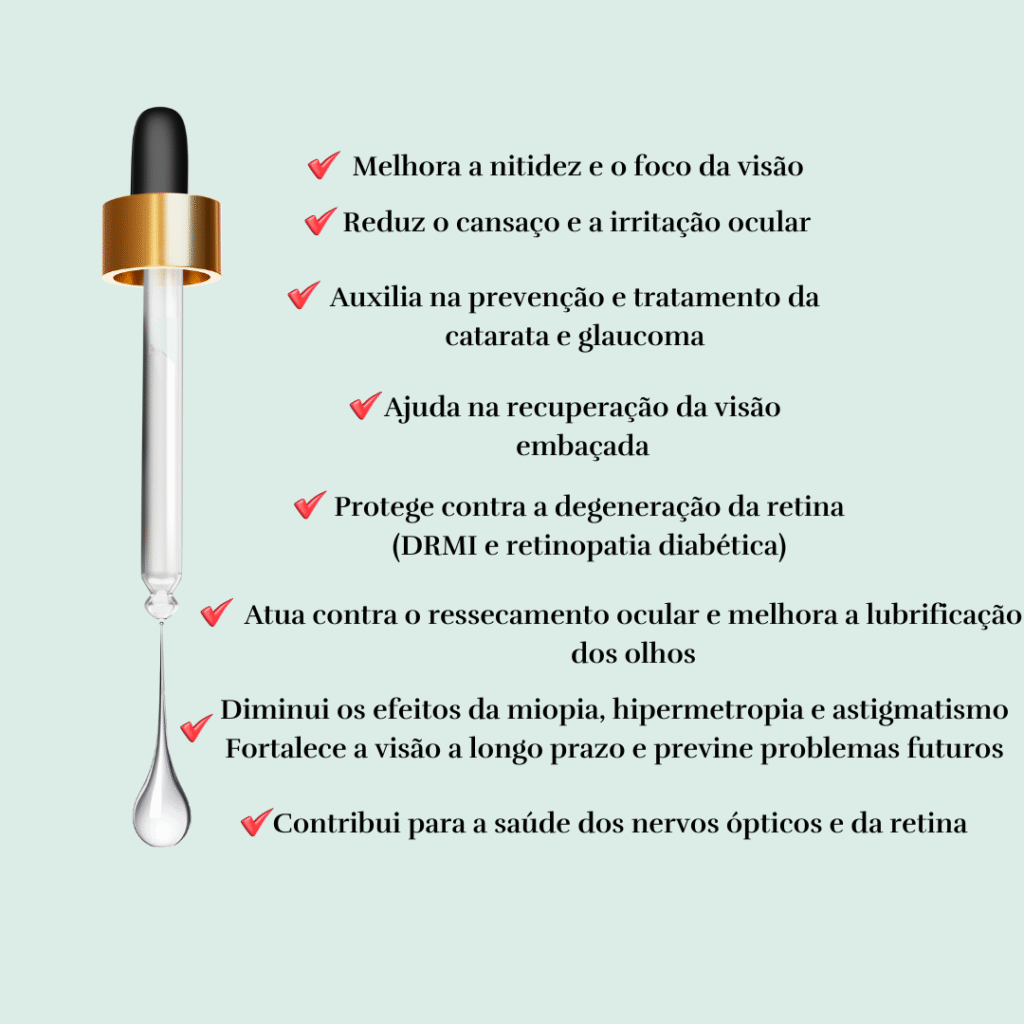

💛 Vision Gold Premium contém uma combinação poderosa de ativos essenciais que:

✔ Eliminam o embaçamento da visão

✔ Restauram a nitidez e o foco

✔ Protegem contra catarata, glaucoma e degeneração ocular

✔ Fortalecem sua visão de dentro para fora

BENEFÍCIOS QUE O VISION GOLD TRARÁ PARA SUA VISÃO:

Melhora a acuidade visual

O Vision Gold Premium

melhora a acuidade visual

e proporciona a nitidez do foco retiniano

dentro do olho humano,

a saúde e funcionamento da

retina e a sensibilidade da faculdade

interpretativa do cérebro.

Veja o Mundo com Olhos Jovens

Com o Vision Gold

seus olhos se beneficiam de uma renovação

celular acelerada, proporcionando

uma visão mais jovem e revitalizada.

Reduz os sinais de envelhecimento ocular

e aproveite uma visão mais clara e vibrante.

Reduz 91,2% a visão embaçada

Usando Vision Gold todos os dias

é possível tratar e restaurar de forma natural,

os danos que a idade nos trás,

promovendo uma visão mais clara.

O vision Gold combate os Raios UV

e também a luz azul.

Desfrute de uma visão nítida.

Trata e protegece contra Catarata

A Catarata é a Opaficação do cristalino

do olho, levando à visão turva.

O betacaroteno pode ajudar a prevenir

a formação de Catarata

ao neutralizar os radicais livres que

danificam as proteínas no cristalino.

O efeito antioxidante do betacaroteno

ajuda a manter a transparência do cristalino

contribuindo para uma visão clara.

Visão Uniforme e Radiante

Você alcançará uma visão clara

e uniforme, com uma nitidez suave

e precisa. Imagine não precisar de

óculos ou lentes para corrigir

as imperfeições visuais!

Ao focar em qualquer objeto, sentirá

a sensação de clareza aveludada

e ao olhar ao redor, terá a certeza

de uma visão impecável e sem distorções.

Conforto e Clareza Ocular!

Você deseja uma visão confortável, clara

e livre de cansaço visual? Acredite, isso é

totalmente possível! Imagine

sentir o conforto e a clareza da

sua visão juvenil novamente, sem aquela

sensação de cansaço e fadiga ocular.

Experimente uma visão revitalizada e descansada,

tirando qualquer aparência de cansaço dos seus olhos.